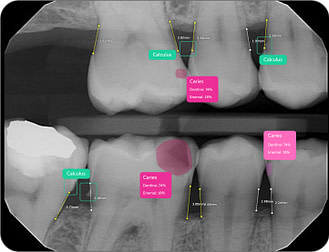

Caries Detection

The best for last and arguably the most well-thought-out feature. Especially with the tooth segmentation mode, which makes it easier for patients to understand their diagnosis and treatment plans.

The system uses two shades of pink to indicate potential caries:

- Light pink: Incipient caries (100% in enamel) - we will often review

- Darker magenta: Caries extending into dentin - we need to restore

The system even provides a percentage breakdown of enamel vs. dentin involvement. I have been blown away by its accuracy while using it, and it makes something that feels quite subjective (reading shades of grey) into a science.

This feature is very useful for patient education and deciding between preventive measures and restorative treatment. However, remember that radiographic evidence alone is not always sufficient for a definitive caries diagnosis.

“ToothParts” in Presentations

The ability to toggle the ToothParts feature during case presentations is one of the most powerful patient education tools I have seen.

Visually distinguishing different tooth structures helps patients better understand their conditions and proposed treatments.

In combination with caries and bone loss AI diagnosis, it really works incredibly well and what I appreciate the most about Pearl is that it seems to be designed with presenting to the patient in mind. As its so simple for someone who is non-dental to understand and follow along.